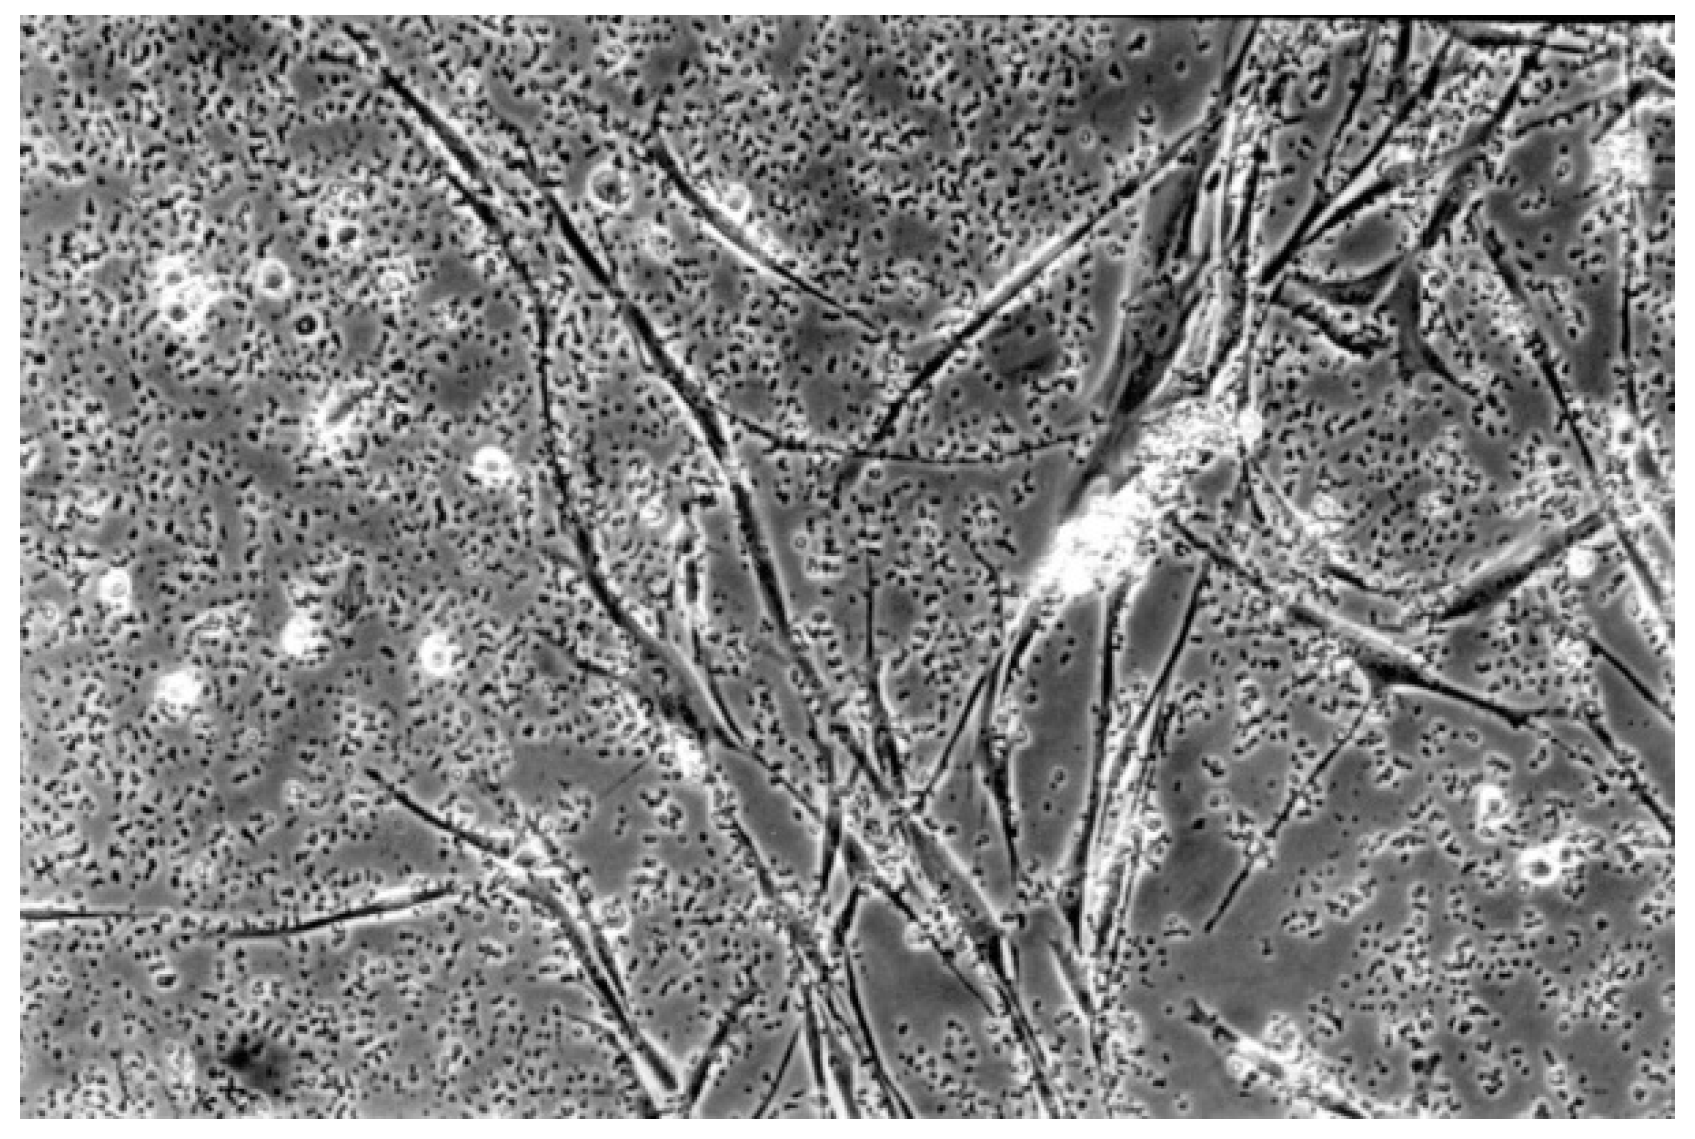

2.2.2. Qualitative Evaluation

| 1 | slight | Not more than 20% of the cells are round, loosely attached and without intracytoplasmatic granules, or show changes in morphology; occasional lysedcells are present; only slight growth inhibition observable |

| 2 | mild | Not more than 50% of the cells are round, devoid of intracytoplasmatic granules, no extensive cell lysis; not more than 50% growth inhibition observable |

| 3 | moderate | Not more than 70% of the cell layers contain rounded cells or are lysed; cell layers not completely destroyed, but more than 50% growth inhibition observable |

| 4 | severe | Nearly complete or complete destruction of the cell layers |